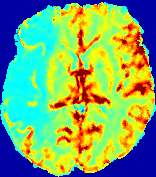

LesionRefer to captionRefer to captionRefer to captionRefer to captionRefer to captionRefer to caption𝐕rgbsubscript𝐕𝑟𝑔𝑏{\bf{V}}_{rgb}Refer to captionRefer to captionRefer to captionRefer to captionRefer to captionRefer to caption𝐕2subscriptnorm𝐕2{\|\bf{V}}\|_{2}Refer to captionRefer to captionRefer to captionRefer to captionRefer to captionRefer to captionRefer to caption3.53.53.52.82.82.82.12.12.11.41.41.40.70.70.70.00.00.0(mm/s)𝑚𝑚𝑠(mm/s)D𝐷DRefer to captionRefer to captionRefer to captionRefer to captionRefer to captionRefer to captionRefer to caption0.0200.0200.0200.0160.0160.0160.0120.0120.0120.0080.0080.0080.0040.0040.0040.0000.0000.000(mm2/s)𝑚superscript𝑚2𝑠(mm^{2}/s)Slice #1Slice #2Slice #3Slice #4Slice #5Slice #6

Figure 4: PIANO feature maps for another patient in the ISLES 2017 training set, where the lesion is located in the right hemisphere. Top row: segmented stroke lesion region (white) on different slices. The corresponding slices for the PIANO feature maps are shown in the following rows.

For a better insight into an estimated velocity field 𝐕𝐕{\bf{V}} and diffusion field 𝐃𝐃{\bf{D}}, we compute the following maps: (1) 𝐕rgbsubscript𝐕𝑟𝑔𝑏{\bf{V}}_{rgb}: Color-coded orientation map of 𝐕=(Vx,Vy,Vz)T𝐕superscriptsuperscript𝑉𝑥superscript𝑉𝑦superscript𝑉𝑧𝑇{\bf{V}}=(V^{x},V^{y},V^{z})^{T}, obtained by normalizing 𝐕𝐕{\bf{V}} to unit length and mapping its 3 components to red, green, blue respectively; (2) 𝐕2subscriptnorm𝐕2\|{\bf{V}}\|_{2}: 222 norm of 𝐕𝐕{\bf{V}}; (3) D𝐷D: scalar field in Eq. 5.

Fig. 3 and Fig. 4 show the PIANO feature maps estimated from two ISLES 2017 patients: all are highly consistent with the lesion in both cases. Details of the blood flow trajectories are revealed in 𝐕rgbsubscript𝐕𝑟𝑔𝑏{\bf{V}}_{rgb} by the ridged patterns and the sharp changes of colors in the unaffected (right) hemisphere, while the flat patterns appearing within the lesion provide little directional information about the velocity and indicate low velocity magnitudes. Velocity magnitudes are more directly visualized via 𝐕2subscriptnorm𝐕2\|{\bf{V}}\|_{2}, from which one can easily locate the lesion where 𝐕2subscriptnorm𝐕2\|{\bf{V}}\|_{2} is low. D𝐷D also indicates lower diffusion values in the lesion, though with less contrast potentially due to the fact that it captures the accumulated effect of CA diffusion at the voxel-level.